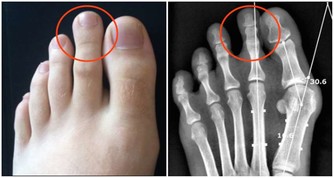

愛放屁且淨放臭屁很可能是患上了足以致命的疾病—大腸憩室炎,尤其是對於長期便秘的人群來說,尤其要注意,便秘的人每次排便都要對腸子施以很大壓力,時間長了,憩室就可能被一個一個擠出來,所以要注意緩解便秘,經常便秘者要趕緊治療,不可小視。平時要多吃一些潤腸排便的纖維含量高的食物, 或者按摩腹部, 飯後半小時適當運動, 加強胃腸蠕動,也有助於改善便秘。

無屁比多屁更危險:

新生兒不放屁, 要檢查是否為無肛症或肛門發育不全。成人無屁, 腹部發脹如鼓, 還要考慮肛門或直腸是否有毛病, 如炎症、腫瘤、便秘、痔瘡等,必要時需要肛門插管排氣。患有腸套疊、腸扭轉、腸梗阻的人無屁,可能多因腸道某處“封鎖”不通。如果不放屁並伴有劇烈的腸絞痛, 必須趕快就醫。此外, 胃穿孔、闌尾炎穿孔形成腹膜炎者, 腹部發硬,觸之劇痛, 也可無屁。